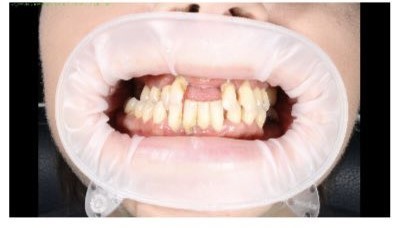

Установка съемного протеза

Специалисты стоматологической клиники «Доктор Дент» изготовили высокоэстетичные съёмные протезы, теперь наш пациент может нормально кушать и снова улыбаться!